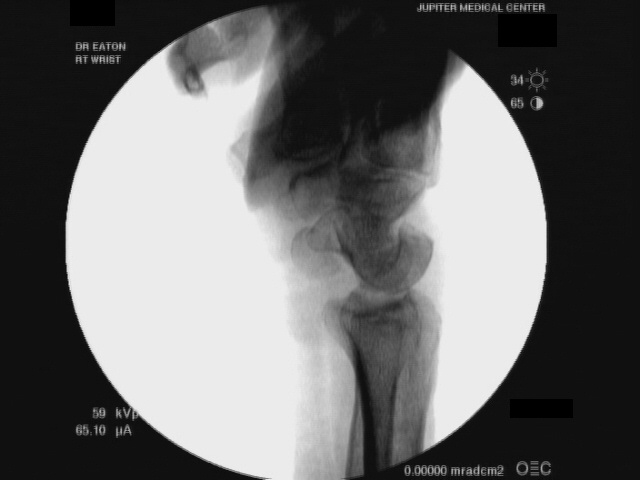

| Fluoroscopy confirms

painless dorsal lunate dislocation, reduced with finger pressure on the

dorsal lunate. This presents a treatment dilemma, as he has full range

of motion, and despite intermittent pain, no limitations of daily

activity. |